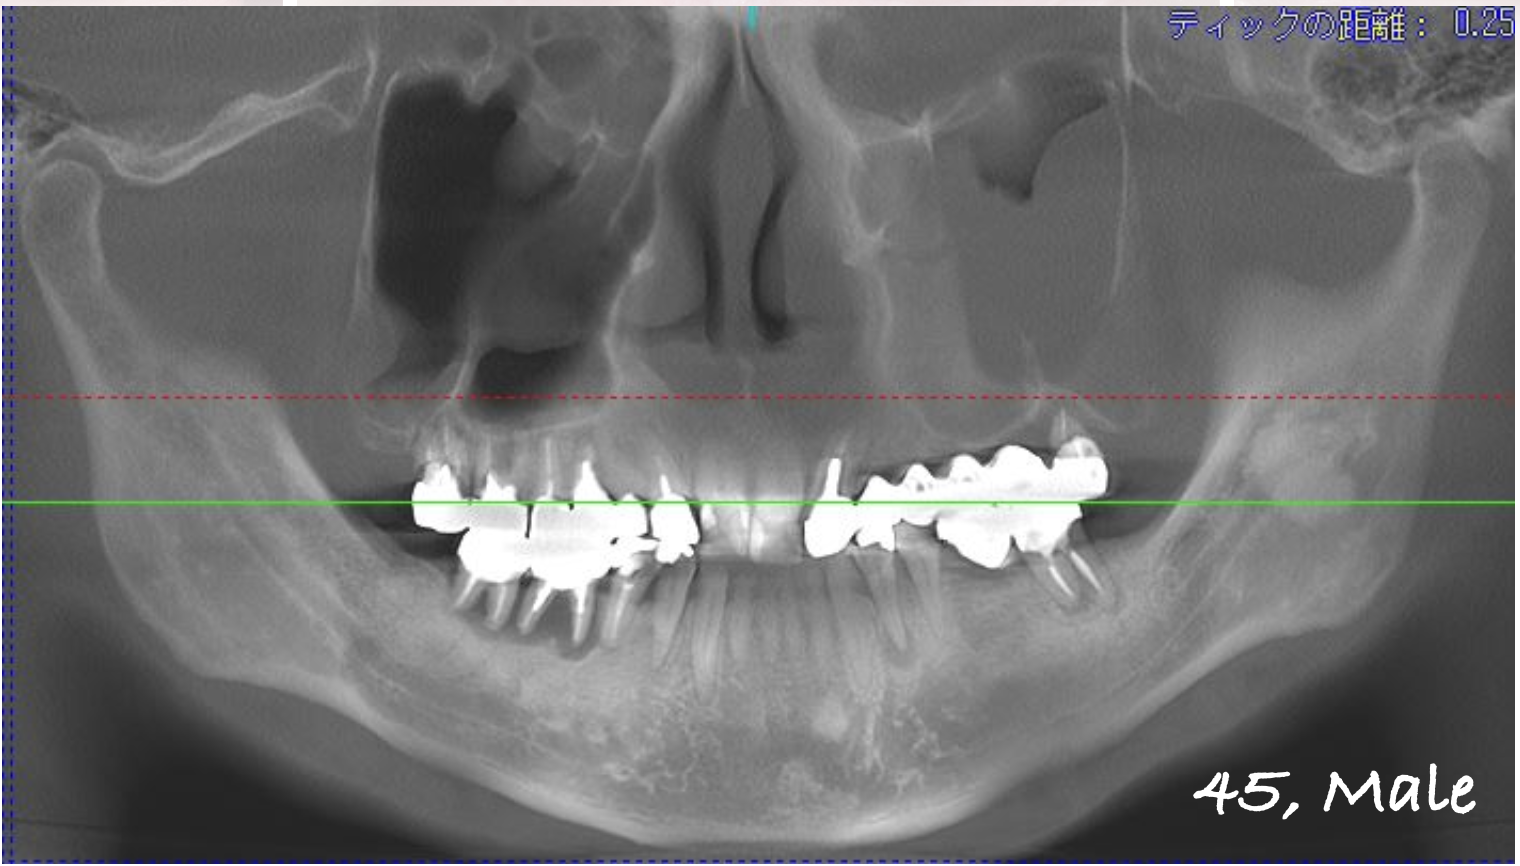

パノラマX線

上顎:インプラントは保存できる状態。

下顎:インプラントを含め全て保存不可能な状態。